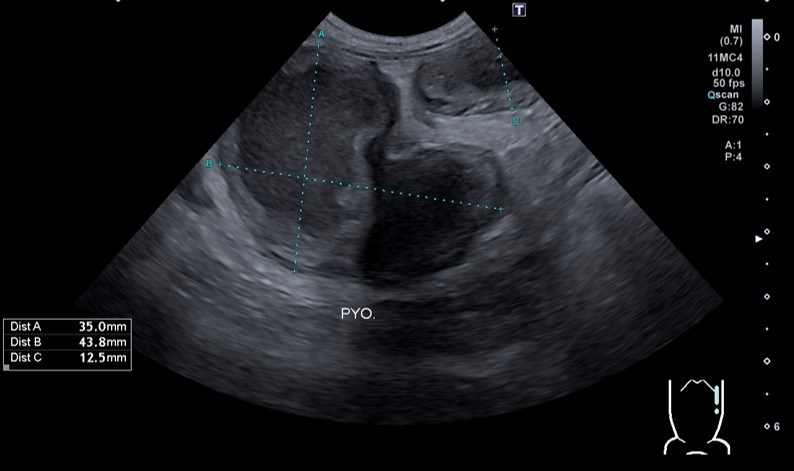

・超音波(エコー)検査

診断を確定するために最も重要な検査です。お腹に超音波を当てることで、液体(膿)でパンパンに膨れ上がった子宮を直接確認することができます。

ぐったりしているという主訴で来院され、レントゲン検査、超音波検査を行った結果、子宮が直径43.8mm(正常な犬では数mm程度)にまでパンパンに腫れ上がっていました。※Bの点線